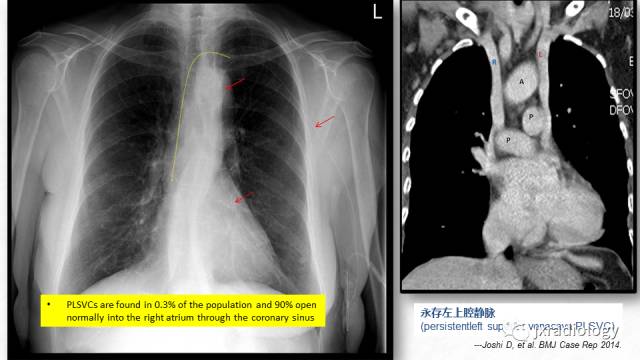

picc放射影像定位

图片尺寸960x540